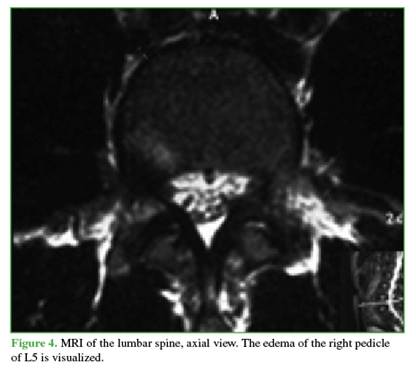

Anteroposterior, lateral, and oblique radiographs of the lumbar spine showed sclerosis of the right pedicle and left-sided spondylolysis at the level of the fifth lumbar vertebra. CT scan revealed, in addition to the findings mentioned above, a discontinuity in the right pedicle, with sclerotic and hypertrophic margins (Figures 1 and 2). Magnetic resonance imaging demonstrated edema in the lumbar pedicle (Figures 3 and 4).

A common feature of pediculolysis is sclerosis of the pedicle, although it remains unclear whether this represents an adaptive phenomenon prior to the fracture or a consequence of it.9 This unilateral sclerosis gives the vertebra an asymmetric appearance on radiological imaging. Computed tomography (CT) undoubtedly allows for better assessment of the lesion, differential diagnosis, monitoring of progression, and, in some cases, therapeutic planning. Characteristic CT findings include a radiolucent line of discontinuity with sclerotic and hypertrophic margins.4 Magnetic resonance imaging (MRI) has high sensitivity for diagnosing these lesions. While it may or may not reveal the fracture line at the pedicle level, it does demonstrate associated edema, which appears hypointense on T1-weighted sequences and hyperintense on T2-weighted sequences.3,4